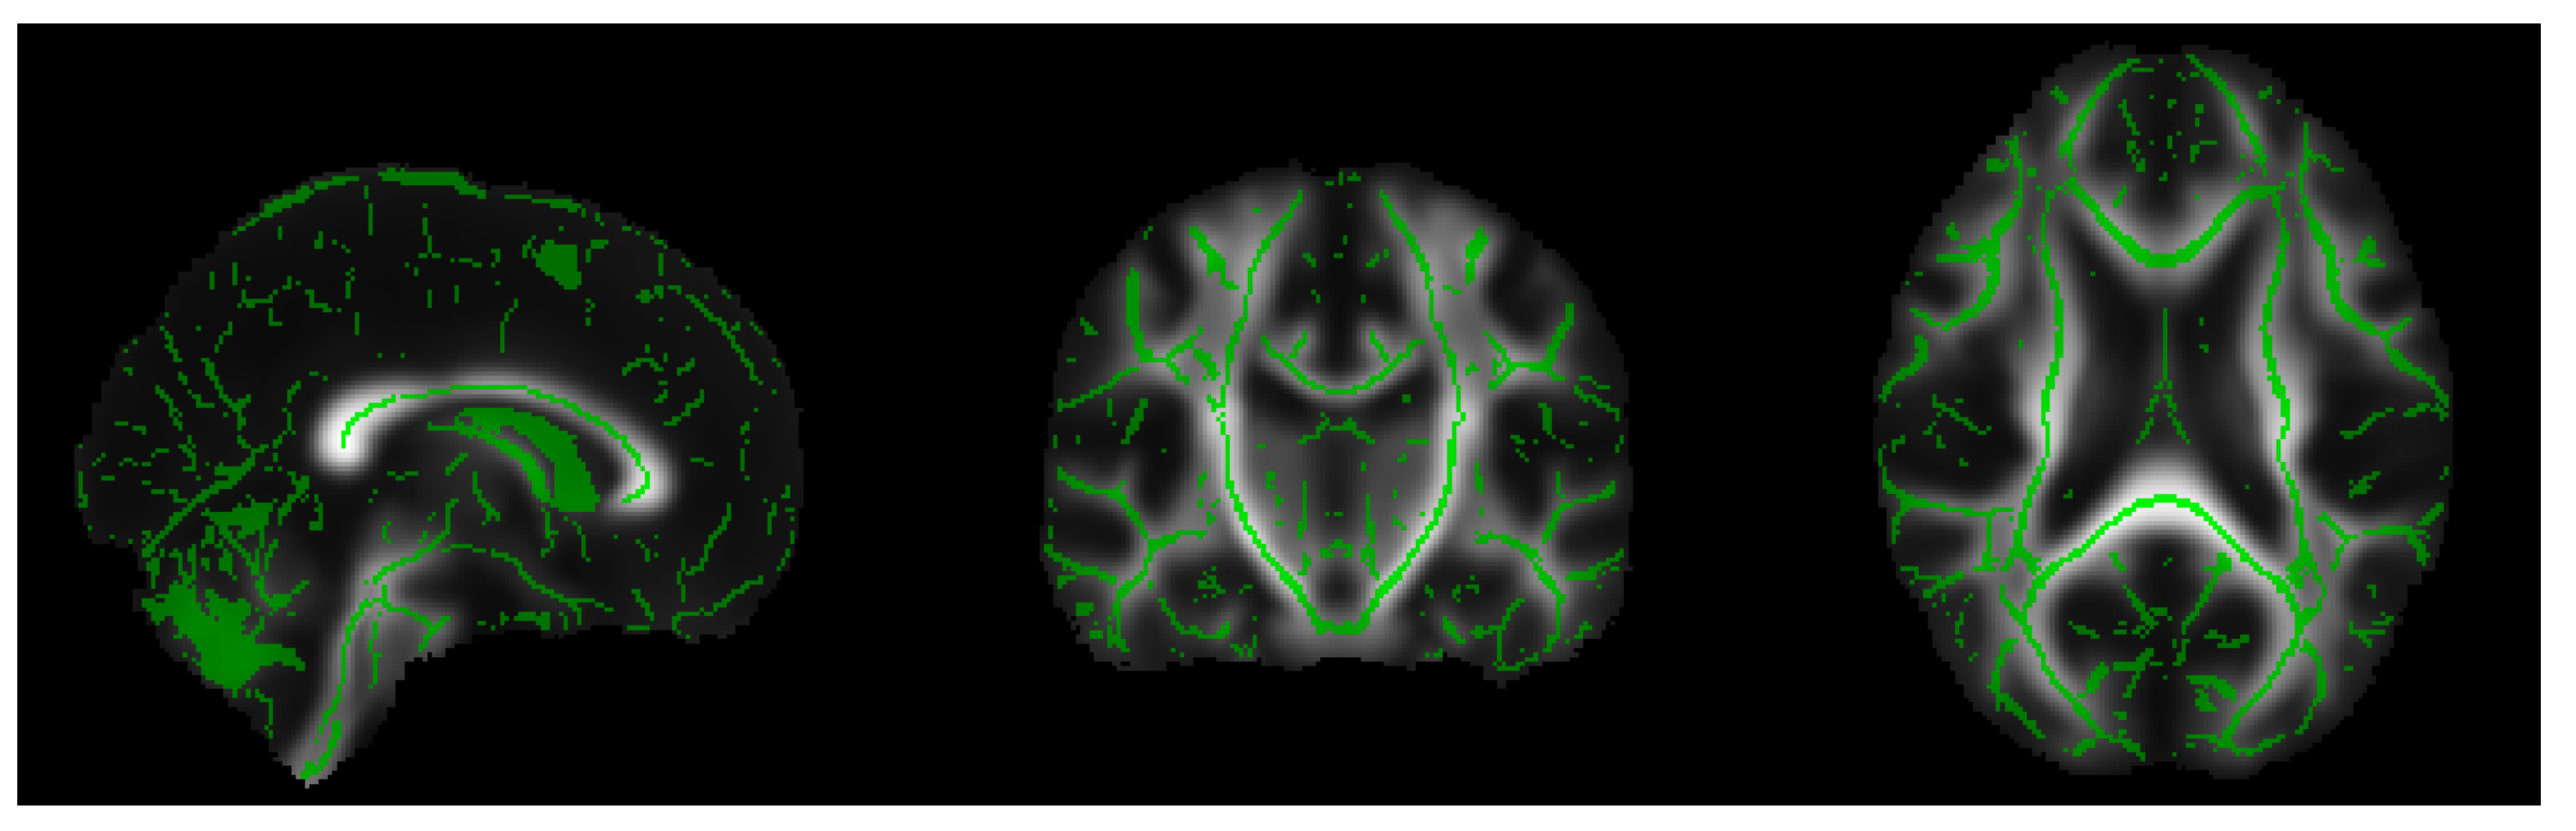

- Extraction of the white matter skeleton: by averaging all the FA maps of the dataset, a mean FA image was obtained, and this result was used to create a mean FA skeleton of WM fiber tracts that were common to all subjects (see Figure 1). A threshold was applied to the mean FA skeleton in order to exclude gray matter and cerebrospinal fluid voxels, and the voxels of the zones characterized by greater inter-subject variability belonging to the outermost part of the cortex.